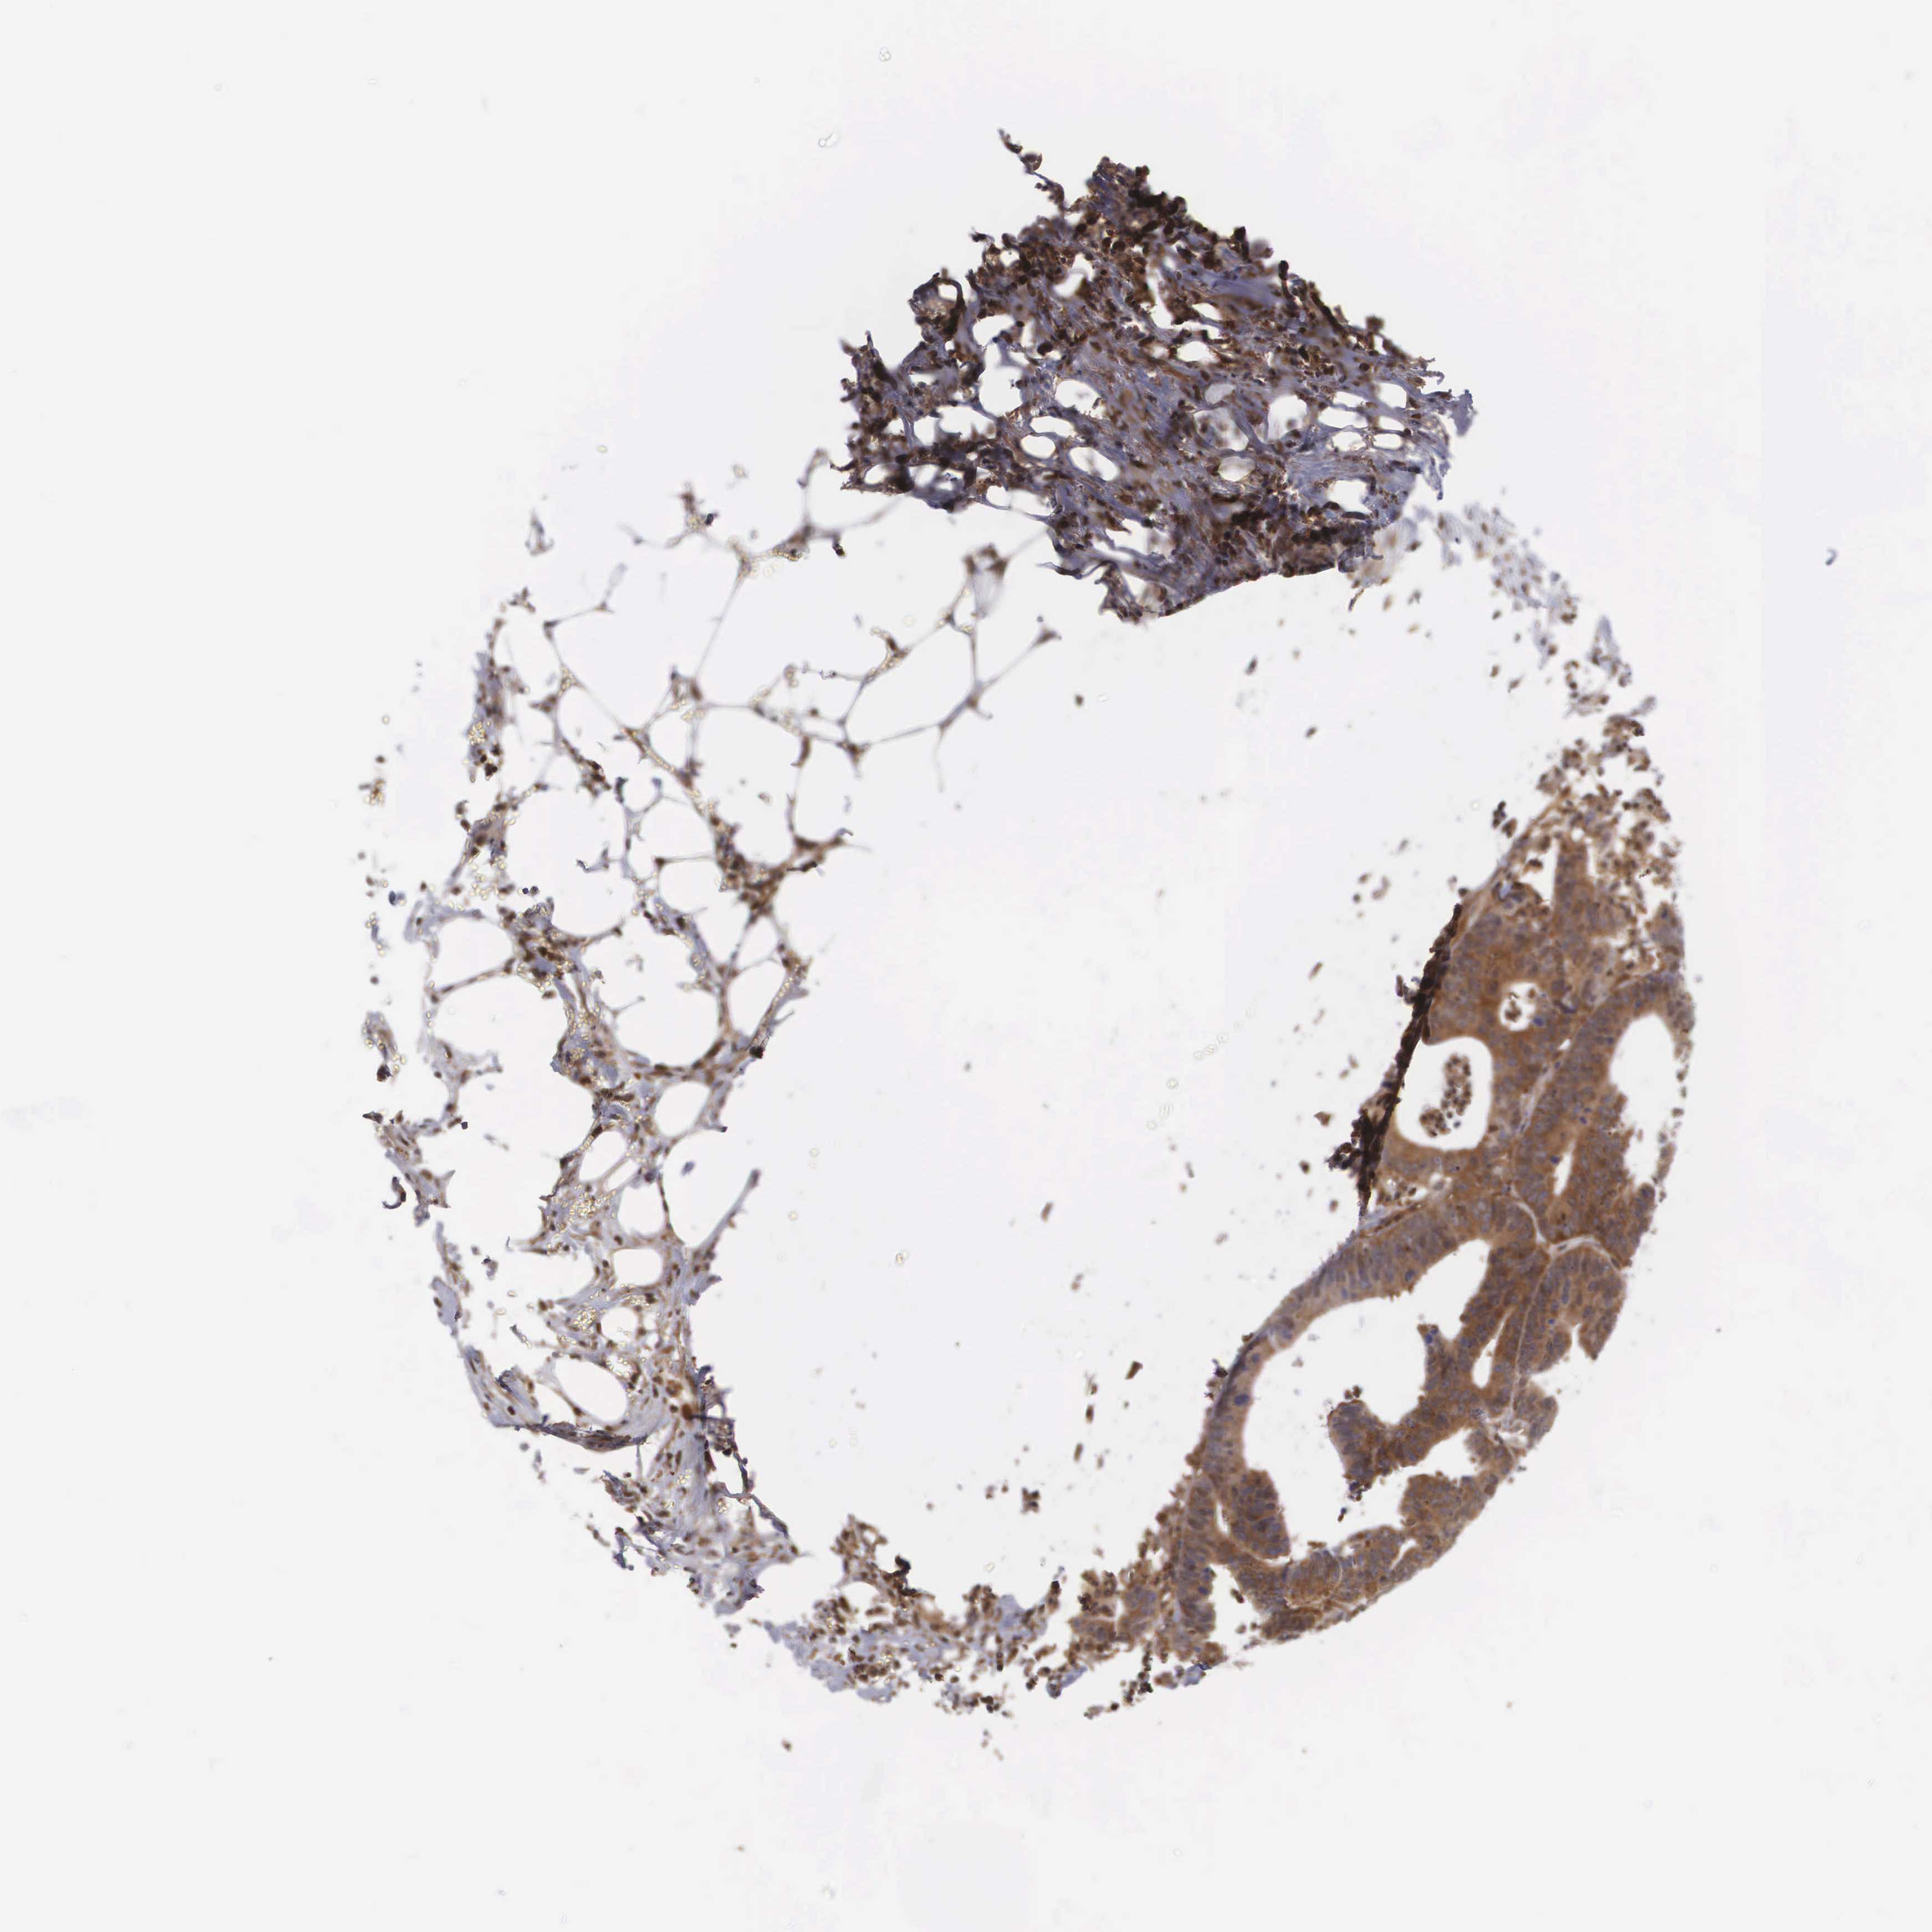

CANCER COLORECTAL CANCER Show tissue menu

ANTIBODIES

AND

VALIDATION